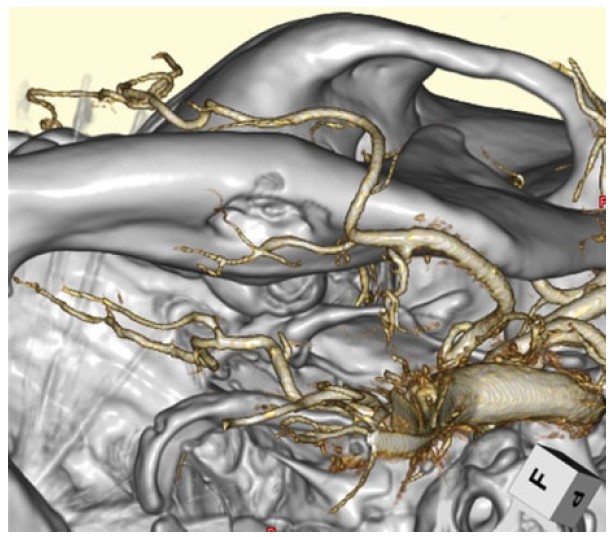

A 36-year-old female was consulted from oral and maxillofacial surgeon. An asymptomatic static bone cavity (SBC) in the submandibular region was identified on computed tomography (CT) imaging of the face and mandible 10 years ago (Figure 1A). No abnormalities in oral function or neurological findings were noted. However, follow-up CT imaging over time revealed enlargement of the bone defect (Figure 1B). Head magnetic resonance imaging (MRI) showed no involvement of soft tissues, such as glandular tissue or muscles: T1 low, T2 low (data not shown). Head angiography revealed a submental artery branching from the facial artery, coursing around the inferior border of the mandible (Figure 2). It corresponded to the outer edge of the SBC. Located at the periphery of the bone defect site, it was thought to be the cause of bone degeneration. Bone deficit had been progressing since youth.

Figure 2: Three-dimensional head angiography. The left mandibular bone and the facial and submental arteries are observed from the left Water’s angle.

The cause and pathogenesis of SBC are still under discussion. Many hypotheses are proposed, such as the mandible bone forming around the submandibular salivary gland during embryonic development; insufficient bone production; abnormal vascular pressure from the facial artery causing necrotic change; and adjacent bone resorption. The most commonly accepted theory is that SBC starts from the pressure of glandular tissue on the mandible’s lingual cortex [6],[11],[12],[13]. The submandibular gland is linked to the posterior variant, while the sublingual gland is linked to the anterior variant, and the parotid gland is linked to both variants of the ascending ramus of the mandible. The bone defect is either empty or contains salivary grand, adipose, connective tissue, muscular, blood vessel or, rarely, lymph nodes [2],[6],[9],[12],[13],[14],[15],[16],[17]. In the present case, the lesion was located in the anterior lingual region, without any other tissue components. The submental artery, branched from facial artery, has been surrounded the bone edge of SBC observed. The arterial pulsatile pressure has been presumed to cause the SBC formation.

The submental artery branches off from the facial artery and supplies blood to the chin region from the inner side of the mandible. Occlusion within this branch is generally not problematic, whereas occlusion of the facial artery itself may cause taste disorders or sensory disturbances in the tip of the tongue. Therefore, during endovascular embolization, it was necessary to reliably guide the microcatheter to the submental artery and occlude that vessel. The submental artery supplies blood to the mental region, along the mandibular midline. Combined with blood flow from the contralateral side, it perfuses the tissue, making the risk of major complications from unilateral embolization relatively low.

There are also case reports of SBC caused by vascular factors [18]. It was thought that pulsatile compression from the artery, transmitted through the soft tissue between the bone and vessel, gradually eroded the mandible.